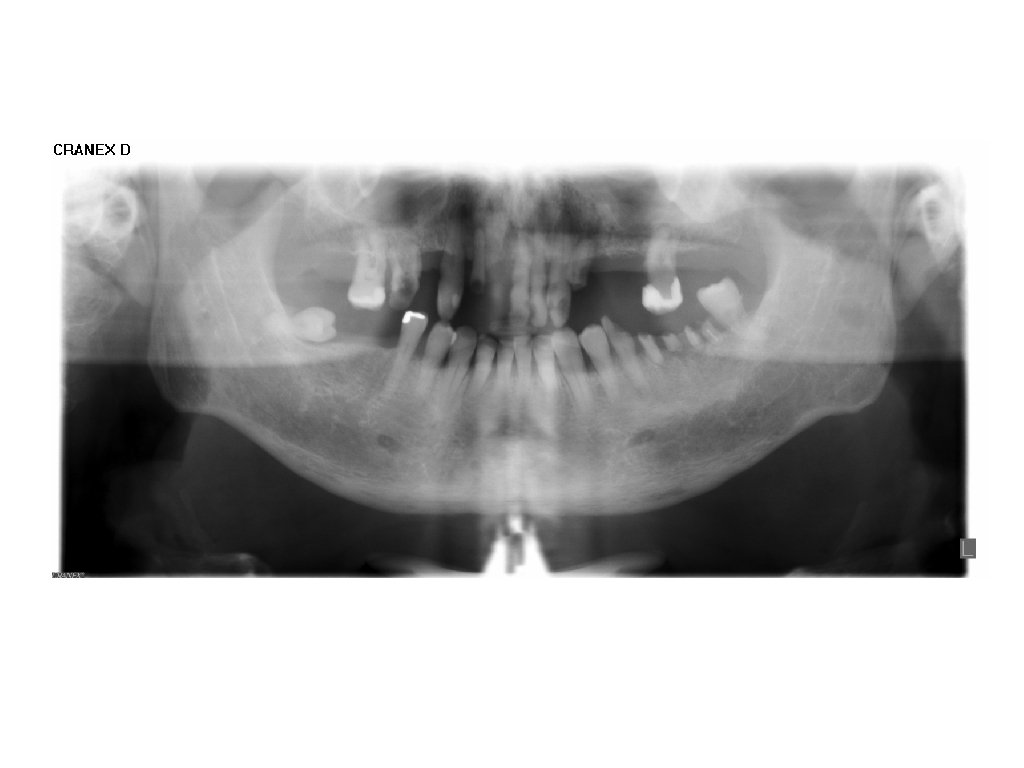

Socialt udsatte